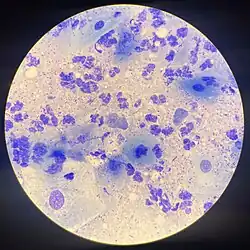

| Chlamydia trachomatis bacteria found in a pap test of the cervix in a case of chlamydia | |